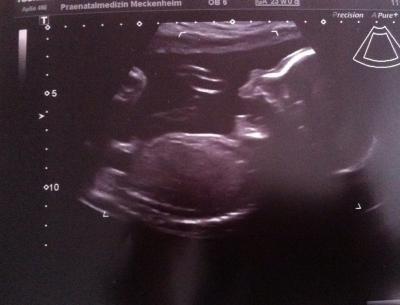

Hallo. Ich wollte euch kurz vom Besuch im Pränatalzentrum berichten. Es ist alles so wie es sein sollte. Alle Organe konnten gut dargestellt werden und sind unauffällig. Der Kleine war dennoch sehr aktiv und liegt gerade mit den Kopf nach unten. Er wiegt ca 500g und ist ca 30cm groß. Der Ultraschall hat ganze 35 Minuten gedauert. Zum Schluss gabs es noch drei Bildchen gratis. Ich zeig euch das schönste. Hier gähnt der Kleine gerade.

Bild zu Organscreening bei 23+0 - Forum für August - Mamis